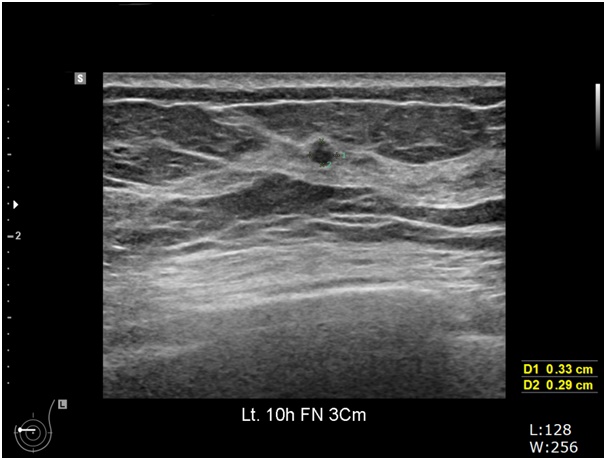

유방에 어떤 증상이 있게 되면 검사는 3가지로 진행되게 됩니다. 첫 번째로 신체검사입니다. 유방을 직접 보고, 손으로 촉진하여 이상의 유무를 확인하게 됩니다. 그 다음으로는 유방 촬영과 유방 초음파가 있습니다. 유방 촬영은 유방 촬영기를 이용하여 유방을 넓게 편 뒤에 방사선을 발생시켜서 촬영하게 됩니다. 유방의 비대칭적인 부분이나 석회화 등을 주로 찾아 보게 됩니다. 유방 초음파는 방사선을 발생시키지 않고 말 그대로 초음파를 발생시켜서 검사를 하게 됩니다. 초음파는 주로 결절, 즉 혹을 잘 찾는 검사입니다. 기본적으로는 이렇게 3가지 검사를 함께 진행하게 되지만 상황에 따라서 어떤 검사를 할 것인가는 차이가 있습니다.

먼저 고려해 봐야 할 것은 나이입니다. 40세 미만 여성에서 만져지는 멍울에 대하여 검사를 한다면, 가장 좋은 방법은 유방 초음파 검사입니다. 유방 초음파 검사는 방사선에 대한 노출이 없고, 검사 자체도 통증이 없는 검사입니다. 검사 자체의 민감도(유방암이 있는 환자에서 검사 유방암으로 진단할 확률) 높은 검사입니다. 초음파 검사를 해보고 그 결과에 따라서 다음 검사 여부를 결정하게 되는데, 초음파 검사에서 만져지는 부위와 일치하는 부위에 멍울을 확인하였지만, 초음파 상에서 보이는 멍울이 특별한 이상을 보이지 않는다면 검사를 종료하게 되고 경과 관찰하게 됩니다. 그렇지만 반대로 유방암이 의심되는 초음파 검사 결과가 나온다면 추가로 유방 촬영을 해봐야 하겠습니다. 그리고 경우에 따라서는 조직 검사도 해봐야 하겠습니다. 그런데 문제는 만져지는 멍울이 있는데, 초음파 검사상 확인되는 결절이 없는 경우입니다. 이러한 경우는 거의 없지만, 이런 경우에는 유방 촬영을 해 보는 것을 권고하고 있습니다.